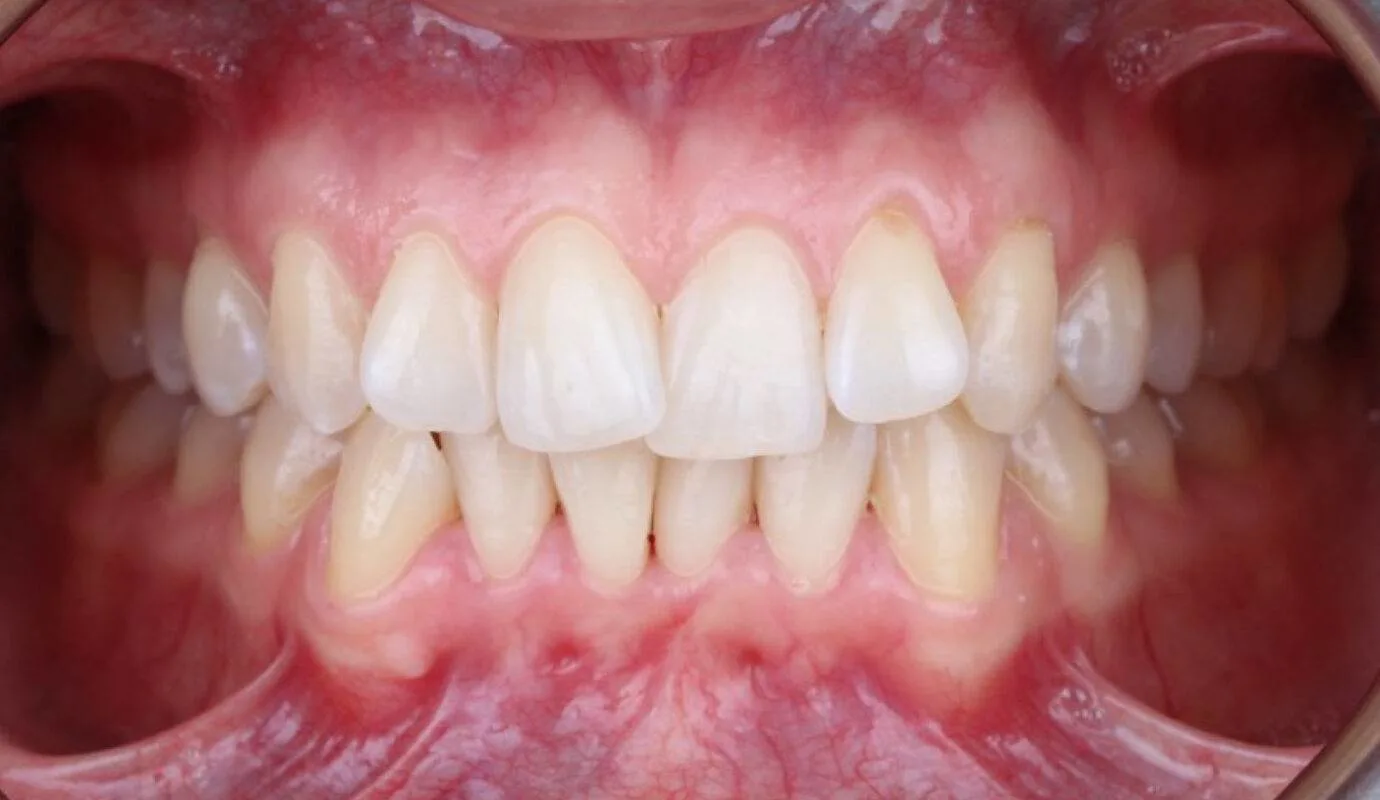

Before midline shift treatment showing misaligned dental midline at SmileBox Clinic After midline shift treatment showing corrected dental alignment at SmileBox Clinic